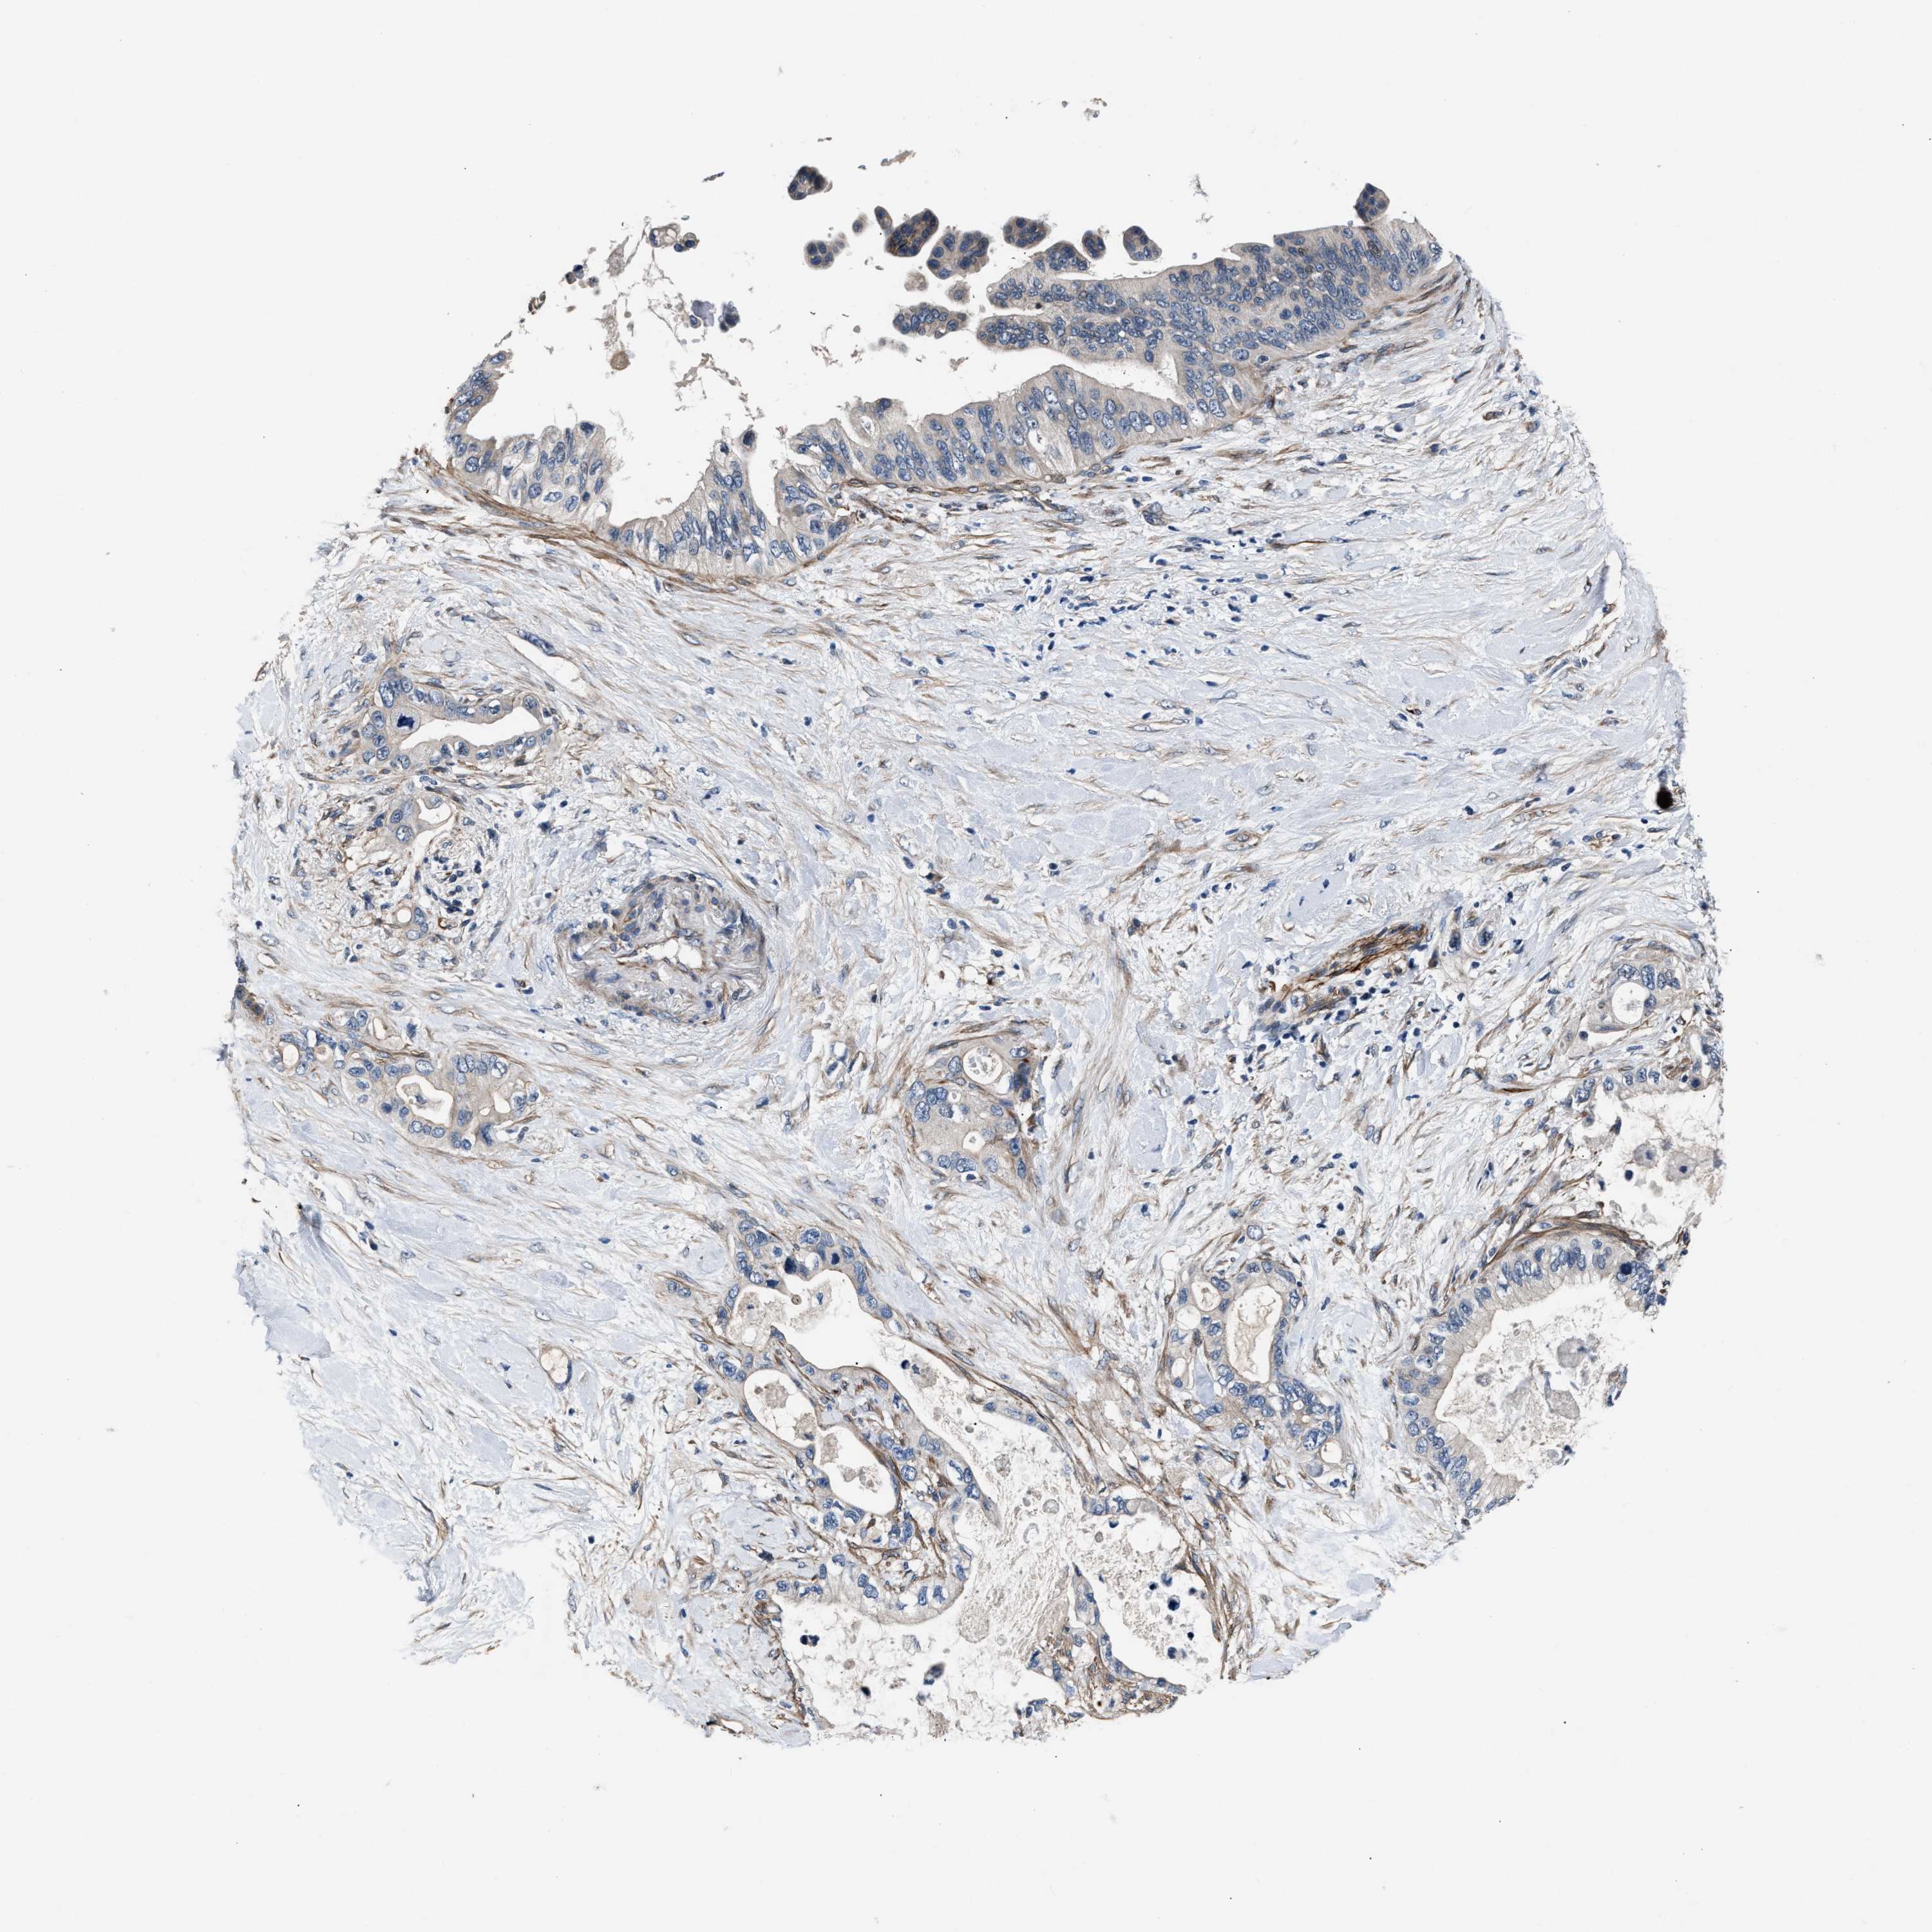

PANCREATIC CANCER - Protein expressioni

A mouse-over function shows sample information and annotation data. Click on an image to view it in a full screen mode. Samples can be filtered based on level of antibody staining by selecting one or several of the following categories: high, medium, low and not detected. The assay and annotation is described here.

Note that samples used for immunohistochemistry by the Human Protein Atlas do not correspond to samples in the TCGA dataset.

Antibody stainingi

Antibody staining in the annotated cell types in the current human tissue is reported as not detected, low, medium, or high, based on conventional immunohistochemistry profiling in selected tissues. This score is based on the combination of the staining intensity and fraction of stained cells.

Each image is clickable and will lead to virtual microscopy that enables deeper exploration of all samples and also displays staining intensity scores, fraction scores and subcellular localization as well as patient and tissue information for each sample.

Antibody HPA020255

Antibody HPA026686

Antibody CAB013512

Staining

High

Medium

Low

Not detected

Intensity

Strong

Moderate

Weak

Negative

Quantity

>75%

75%-25%

<25%

None

Location

Nuclear

Cytoplasmic/membranous

Cytoplasmic/membranous,nuclear

Adenocarcinoma, NOS

Adenocarcinoma, metastatic, NOS